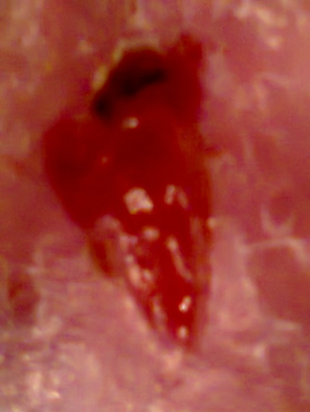

Zustand vor der ersten Behandlung mit Schwellung

Detail nach der ersten Wundhandlung

Schlankes Bein nach sechs Wochen, geheilt!

Nach nur sechs Wochen war das Ulkus von innen heraus sauber verheilt. Von da an bekam der Patient nur noch einmal pro Woche Lymphdrainage.

Nach nur sechs Wochen war das Ulkus von innen heraus sauber verheilt. Von da an bekam der Patient nur noch einmal pro Woche Lymphdrainage. Seine körperliche Leistungsfähigkeit hat sich stetig gesteigert, der Patient hat sein Gewicht reduzieren können, Asthmaanfälle sind nicht mehr aufgetreten.